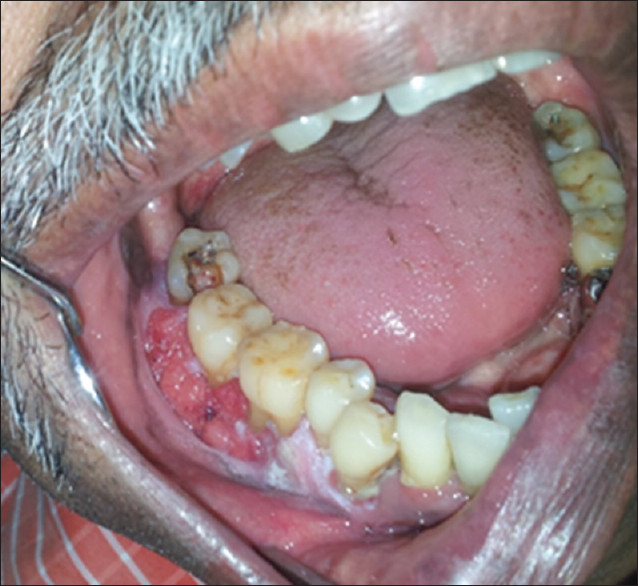

Verrucous carcinoma is an uncommon cancer that often develops in an area of extreme irritation or inflammation with symptoms of cauliflower-like lesions. It's so rare that the American Cancer Society says it accounts for less than 5% of oral cancers. The most typical place for it to appear is within the oral cavity — or the larynx, nasal cavity, and throat. Patients with ill-fitting dentures, oral ulcerative areas, chronic candidiasis, and those who regularly smoke, chew tobacco, and consume alcohol are prone to develop verrucous carcinomas.

According to the American Cancer Society, verrucous carcinoma can easily be picked off. This means it's pretty slow-moving and rarely spreads throughout your body. That's good news. The bad news — it can grow deep within your oral tissue. A proper oral cancer screening with your dentist will help determine if you've developed any of these cancerous lesions. If you have developed verrucous carcinoma, you should seek treatment and immediately remove the lesions and surrounding normal tissue.